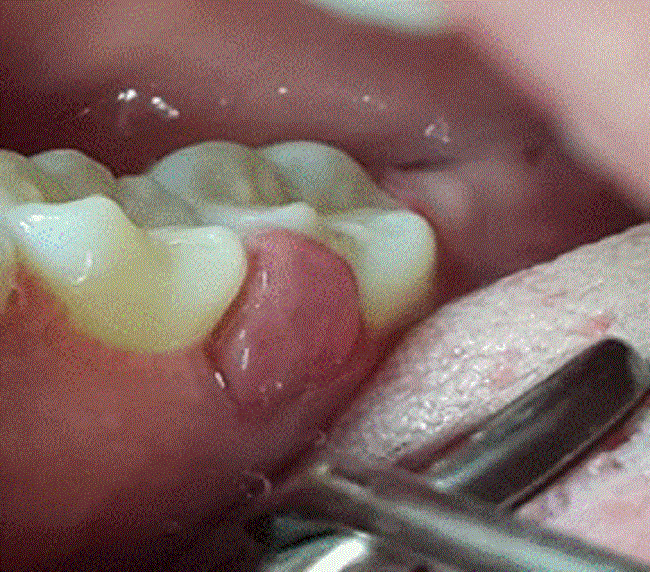

Paciente femenina de 24 años, de 6 meses de embarazo, con aparatología ortodóntica, sin antecedentes médicos de interés y quien es remitida a estomatología del servicio de ginecología por tener múltiples lesiones tumorales en encía, de 3 meses de evolución, acompañados de gingivorragia severa, espontánea y persistente en zonas posteriores de área mandibular derecha, cuyo sangrado aumentaba con el cepillado o con el consumo de algunos alimentos. Paciente refirió que le habían realizado 3 cauterizaciones en más de una lesión y una escisión quirúrgica convencional con recidiva y aparición de nuevas lesiones en Nencías adyacentes, lo que le imposibilitaba la masticación, el habla y el mantenimiento de la higiene oral entre otros. En la evaluación clínica se observó: lesión tumoral en encía interdental lingual que involucraba los dientes 46 y 47, pedunculada, de consistencia firme, asintomática, de 2.5 mm de diámetro y sangrante a la palpación foto 1; también se observaron múltiples lesiones tumorales de aspecto granulomatoso, eritematosas de 0.3 mm a 0.5 mm con deformidad de varias papilas gingivales y descamación del tejido.

Lesión tumoral recidivante y sangrante superficial

Foto 1

Fuente: propia de las y los autores.